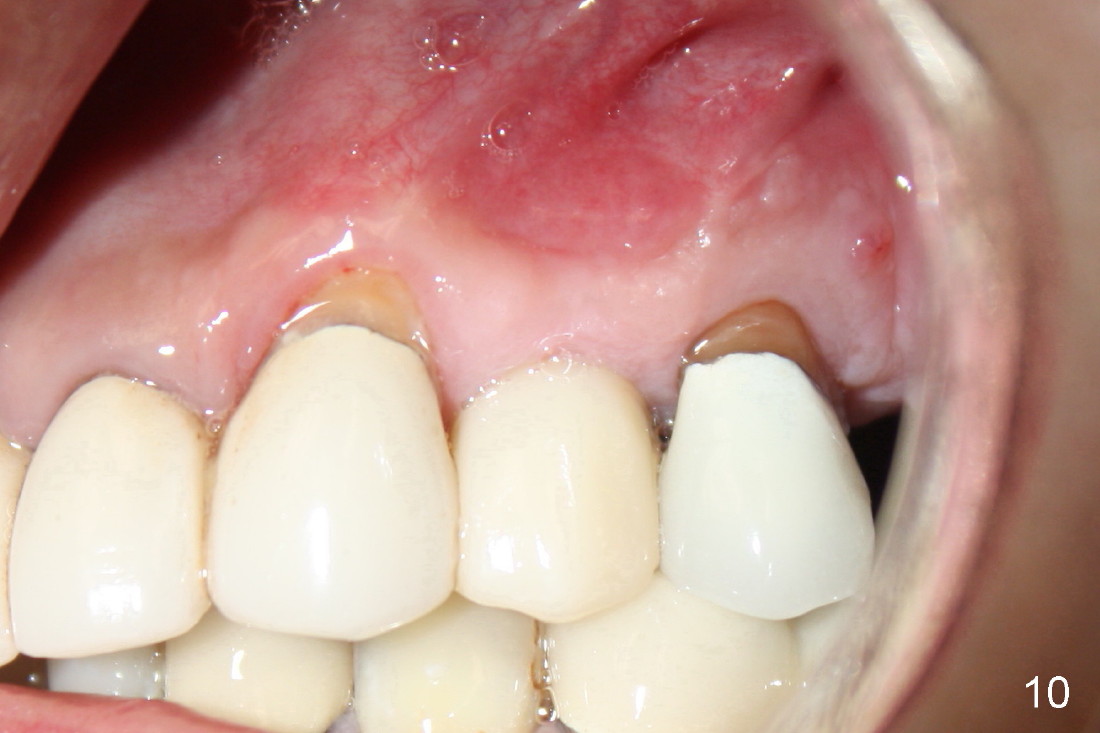

A 50-year-old man has mild pain in the upper left 1st bicuspid 3 years after root canal retreatment with placement of two posts (Fig.1). Findings of clinical exam are consistent with root fracture (Fig.2). Extraction reveals two fused roots (Fig.3,4). Probing indicates that the buccal plate is defective. Osteotomy is initiated in the palatal socket with a 2 mm pilot drill, followed by 2.5 and 3.0 mm reamers and 4.5x20 mm tap. The septum appears to have been pushed buccally (Fig.5 *) and form a new buccal wall (partially, strengthened by bone graft mentioned below) for the implant to be placed. The implant (4.5x20 mm) is placed in the palatal socket (Fig.6 *) with insertion of an abutment (A: 3.5x5 mm 0º), while a mixture of autogenous bone (harvested from reamers) and Synthograft (Bicon) is placed in the shrunken buccal socket (Fig.7; using allograft may decrease postop bony shrinkage). The bone graft is then contained by an immediate provisonal without collagen membrane or flaps. The patient is doing well postop. The gingiva is healthy (Fig.8*) when the provisional is removed 3 months postop with normal papillae (Fig.9 arrowheads). It remains the same 1 month post cementation (Fig.10,11). For further follow up, see immediate implant of the tooth #13.